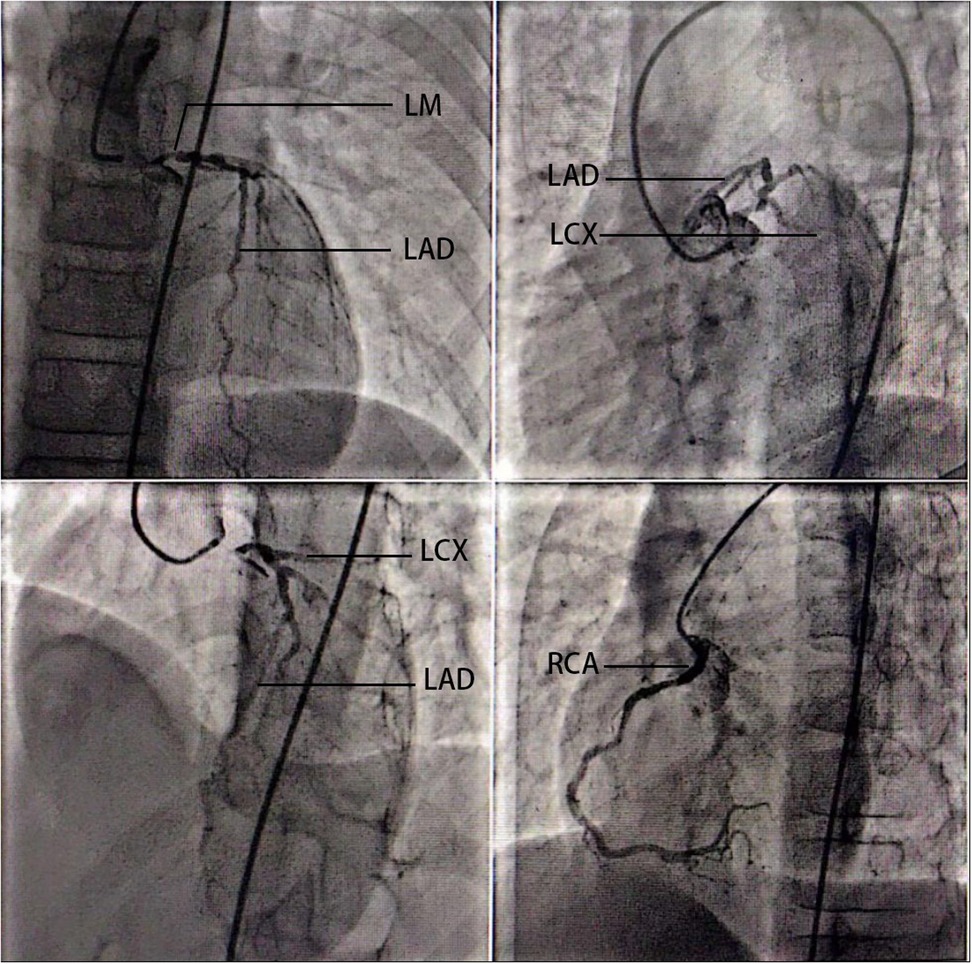

Familial hypercholesterolemia (FH), particularly homozygous or compound heterozygous forms, predisposes individuals to premature cardiovascular disease due to severely elevated low-density lipoprotein cholesterol (LDL-C). This case report describes a 14-year-old male with compound heterozygous pathogenic variants in the LDLR gene, diagnosed with FH with a strong family history of hypercholesterolemia. Despite early initiation of statins, the patient developed progressive angina pectoris. Coronary angiography revealed critical stenosis in the left main arteries, necessitating urgent coronary artery bypass grafting (CABG). Arterial vs venous conduit selection in pediatric HoFH warrants explicit rationale. Postoperatively, LDL-C levels remained elevated but were managed with adjunctive therapies, including PCSK9 inhibitor. Genetic testing confirmed compound heterozygosity, underscoring the aggressive nature of LDLR dysfunction. This case highlights the challenges of managing severe FH in pediatric patients, emphasizing the role of early genetic diagnosis, multimodal lipid-lowering therapy, and timely surgical intervention to prevent life-threatening complications. It also reinforces the necessity for lifelong monitoring and novel therapeutic strategies in compound heterozygous FH cases. This report contributes to the limited literature on CABG in pediatric FH, advocating for a multidisciplinary approach to optimize outcomes in this high-risk population.